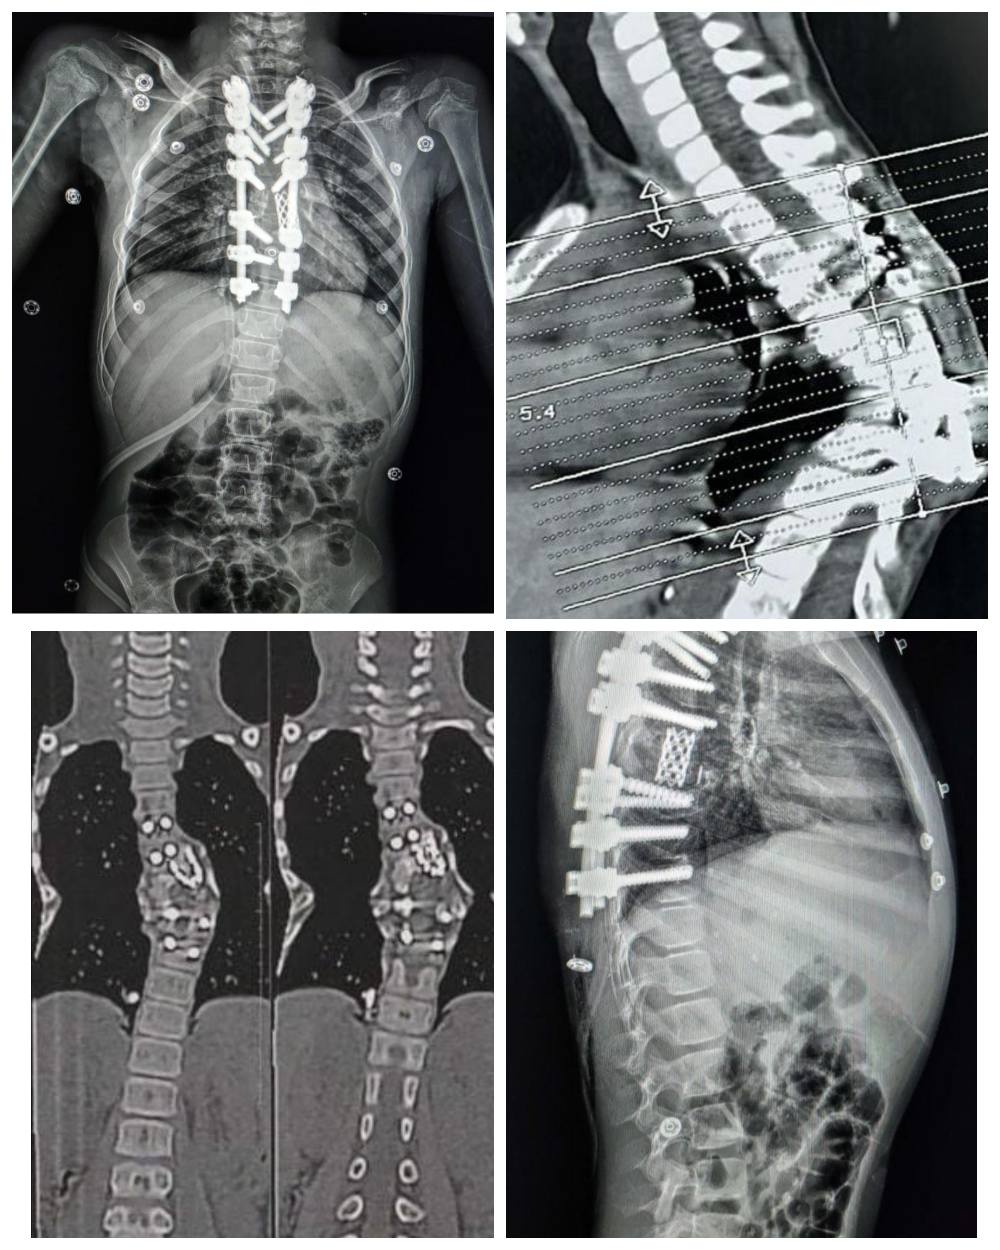

كان مستشفى الإصابات قد استقبل طفلة تعاني من تحدب شديد وصل إلى 85 درجة نتيجة لدرن فقري سابق، وهو ما كان يهدد حركتها ونموها بشكل طبيعي.

كان التشوه ناتجا عن درن في العمود الفقري، وقد زاد الأمر تعقيدا بسبب وجود جراحة سابقة، أجريت لها بإحدى المستشفيات، لتثبيت الفقرات بواسطة مسامير وأعمده وقفص معدني، وإلتئام كامل للفقرات في وضع معيب، مما أدى إلى حدوث تحدب واعوجاج حاد في الفقرات الظهرية، ليقرر الفريق الطبي الذي ضم كل من، الدكتور عمرو حاتم، مدرس جراحة العظام والعمود الفقري، والطبيب محمد خالد، مدرس مساعد بالقسم، والدكتور شادي نادي، أخصائي جراحة العظام والعمود الفقري، والطبيب خالد محسن، مدرس مساعد بالقسم، والطبيب مينا مفدي، نائب بالقسم، والطبيب محمد جمال نائب بالقسم، ويعاونهم فريق من قسم التخدير جاء تحت إشراف الأستاذة الدكتورة هالة سعد رئيس القسم، وضم، الدكتور محمود فيصل، مدرس التخدير والعناية، والطبيب محمد رفعت، مدرس مساعد بالقسم، والطبيب لؤي جمال، مدرس مساعد بالقسم، والطبيبة سارة جمال، نائب بالقسم، ومن هيئة التمريض، الأستاذة هاجر محي، والأستاذ محمد بدر، والأستاذ عمر مصطفى، بإجراء جراحة دقيقة للغاية بسبب صغر سن الطفلة وشدة التشوه، لاستعدال التشوه مع تثبيت الفقرات بدقة، وقد تطلبت الجراحة تقييمات وقياسات معقدة لضمان تحقيق تصحيح كبير دون إلحاق ضرر بالأعصاب الطرفية.

كما قام الفريق الطبي باستخدام جهاز مراقبة الأعصاب، وهو تقنية حديثة متقدمة لجراحات العمود الفقري، وتعد الأولى من نوعها بصعيد مصر، لإجراء شق عظمي لفقرتين من الفقرات الظهرية، واستعدال وتثبيت الفقرات بمسامير فقرات وأعمده وقفص كربوني، بالإضافة إلى ذلك، استخدم فريق التخدير تقنيات حديثة وغير تقليدية سمحت بالمراقبة الفسيولوجية اللحظية للأعصاب والعضلات طوال فترة العملية.

وبفضل هذه الجهود من الفريق الطبي، تم تصحيح التشوه بنجاح، وخرجت الطفلة من العملية في حالة مستقرة، وعادت إليها الحركة بصورة طبيعية.